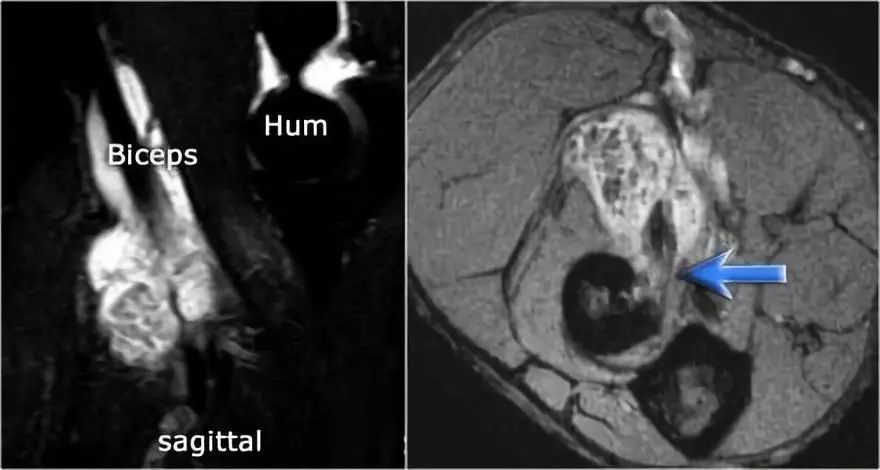

远端肱二头肌肌腱的病理学很像跟腱的病理学。可以有退变,部分撕裂和完全撕裂带或不回缩。以下是73岁男性的超声图像,他们在举起一个盒子时经历了突然的疼痛和撕裂的感觉。在肘关节前方有前旋和旋后疼痛,前方有压痛。

没有瘀斑或可触及的肿块。在矢状图像上,肌腱变厚,但远端肌腱丢失。

在矢状图像上,看起来肌腱完全是刺,但继续下一个图像。

● 远端肱二头肌肌腱撕裂:有完全撕裂,因为如果我们一直跟随肌腱进入桡骨结节,我们可以看到肌腱不附着在那里(绿色箭头)。只有流体。● 肌腱不缩回的原因是因为广泛的萎缩性肌腱 - 也被称为lacertus fibrosus - 仍然完好无损(红色箭头)。● 远端肱二头肌肌腱不仅插入到桡骨结节,而且还通过褶皱纤维进入前臂内侧屈肌旋前肌块的筋膜。

当腱膜也thorn时,肌腱缩回,并且由于收缩的二头肌造成手臂明显肿胀。远端二头肌肌腱撕裂是一种罕见的损伤。大约有5%的肱二头肌受伤。这是肘部弯曲时手臂突然伸展的结果。近端肱二头肌腱撕裂更常见。通常是二头肌的长头完全撕裂。

下面这是另一个例子。在T1W图像上有一些增厚和一些中间信号。这可能是肌腱变性,但总是看T2W图像寻找撕裂。在这种情况下,有部分撕裂。

下面是另一种情况。在矢状图像上,我们不确定可能的撕裂。也许只有一些肌腱炎或肌腱炎。轴向图像显示部分撕裂(红色箭头)。

始终确保你的轴向扫描一直到结节,因为你太早停止,就像在这种情况下,你只会看到增厚的肌腱和一些液体,但你不确定可能的撕裂。